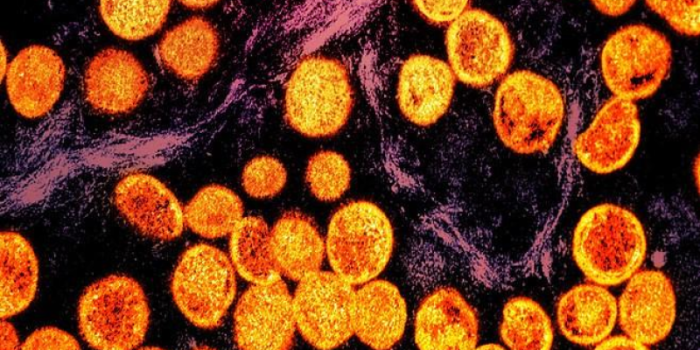

A new study uncovers “silent” mpox circulation in Nigeria, while another concludes that 58% of mpox patients still have signs or complications up to 1.5 years after diagnosis.

For the first study, published today in Nature Communications, researchers from the University of Cambridge and Nigeria analyzed stored blood samples from 176 healthy Nigerian adults who had participated in COVID-19 vaccine studies, including health care workers sampled in 2021 and community volunteers sampled in 2023. Participants hadn’t received mpox or smallpox vaccines as adults and had no known exposure to mpox.

The team measured responses to six different mpox virus antigens, or structural parts of the virus to which the immune system responds, allowing detection of both the strength and scope of immune responses.